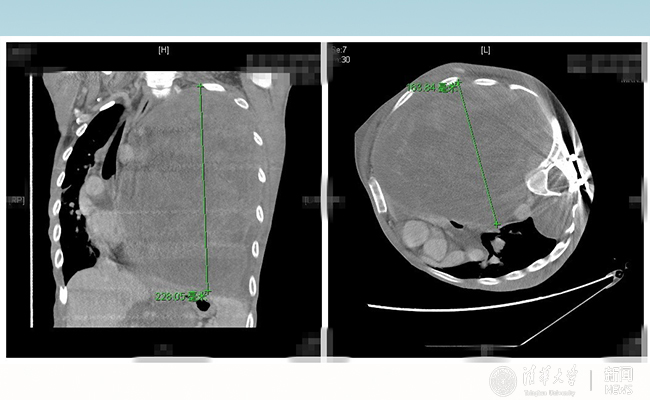

2016.10新葡萄长庚多学科助力胸外科成功切除巨型神经纤维瘤

新葡萄长庚医院多学科助力胸外科手术,成功帮28岁的患者“小飞”切除巨型神经纤维瘤,帮助重病的患者重生。